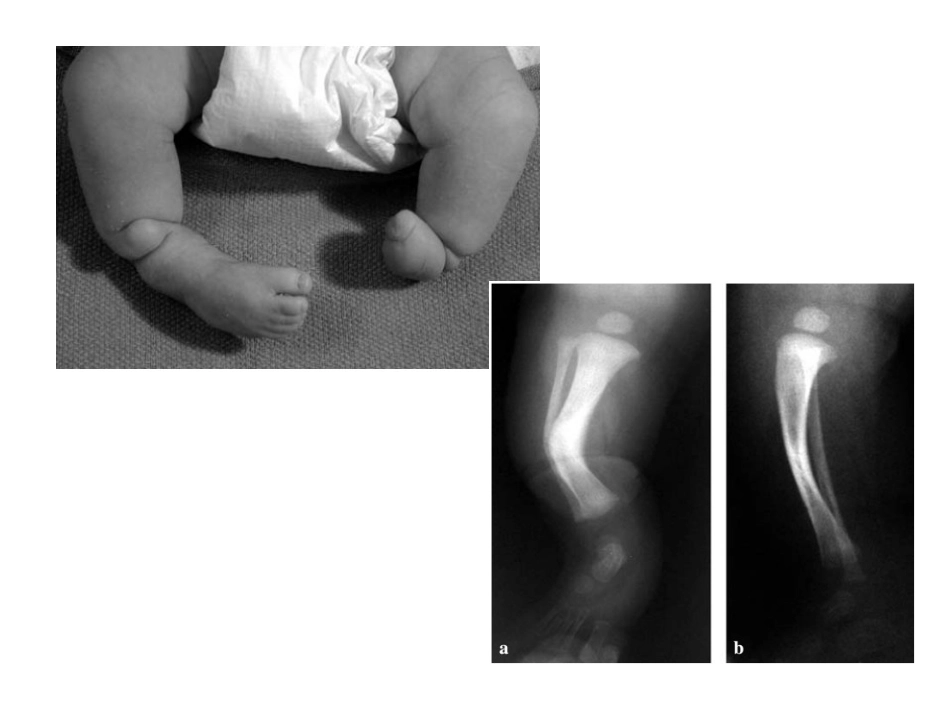

先天性胫骨假关节概念•先天性胫骨假关节(congenitalpseudarthrosisofofthetibia,CPT)是发生在儿童的一种罕见疾病•是一种特殊的骨不连,与神经纤维瘤病有一定关系•是由于天生或发育异常导致的胫骨畸形,表现为胫骨成角畸形、髓腔狭窄或者囊肿等,最终形成不愈合的假关节。•在所有儿童先天性疾病中先天性胫骨假关节可能是最难治疗的之一,没有标准的治疗方式分型•较多,临床指导性较差•多采用boyd分型分型•Ⅰ型:出生时就出现胫骨缺如或胫骨向前弯曲。可有其他先天性畸形。分型•Ⅱ型:此型最为多见,常伴有神经纤维瘤病,预后最坏。•出生时胫骨有前弯的同时有假关节或伴有葫芦状(沙漏)狭窄。•在2岁前可有自发性骨折或轻伤引起骨折,统称为高危胫骨。•骨呈锥状、圆形和硬化状,髓腔闭塞。•在生长期,骨折复发很常见,随着年龄增长,骨折次数将减少,至骨骺成熟,骨折也不再发生。分型•Ⅲ型:较Ⅱ型为少,通常在胫骨中1/3和下1/3交界处发生天性囊肿。•胫骨向前弯曲可先或者后于骨折。•治疗后再发生骨折的机会小。分型•Ⅳ型:在胫骨中1/3和下1/3交界处有硬化段,并发生假关节。•髓腔部分或完全闭塞。•在胫骨皮质可发生不全骨折或应力骨折,逐渐扩展到硬化骨,待折断后,不会再愈合,骨折处增宽而形成假关节。•这类骨折预后较好,在骨折成熟不足之前治疗,效果较好。分型•Ⅴ型:在腓骨发育不良时,胫骨产生假关节,两骨的假关节可同时发生。•若病损限于腓骨,预后较好。•若病损发展至形成胫骨假关节,则其发展过程类似Ⅱ型。分型•Ⅵ型:这极少见。•因骨内神经纤维瘤或Schwann'scell瘤而引起假关节。•预后取决于骨内病损的侵袭性和治疗。治疗•取决于患儿年龄及是否再次骨折•开始行走后腿部应该使用蚌壳样支具加以固定和保护直至骨骼成熟•发展为假关节后,必须手术治疗•髓内固定及重建力线是手术的两个基本原则•假关节切除,骨短缩,补充植骨对手术成功有帮助•最坏的治疗结果是截肢,且比例不低手术方式•植骨-髓内棒-外固定架联合手术髓内棒联合植骨髓内棒联合Ilizarov环形外固定架包裹式自体髂骨植骨联合手术•Masquelet手术•Burnei手术•四合一骨融合术•MSC移植•药物与外科手术联合治疗BMP、BP、rhBMP和BP联合应用治疗•Intramedullarynailingassociatedwithabonegraft治疗•Intramedullarynailingassociatedwithabonegraft治疗•Vascularizedbonetransfers治疗•Ilizarovtechnique治疗•Ilizarovtechnique治疗•Inducedmembraneandspongyautologousgraft治疗•Osteoinduciveproteinsorbonemorphogeneticproteins治疗治疗并发症•踝关节及足的僵硬•骨折•踝外翻畸形•胫骨短缩